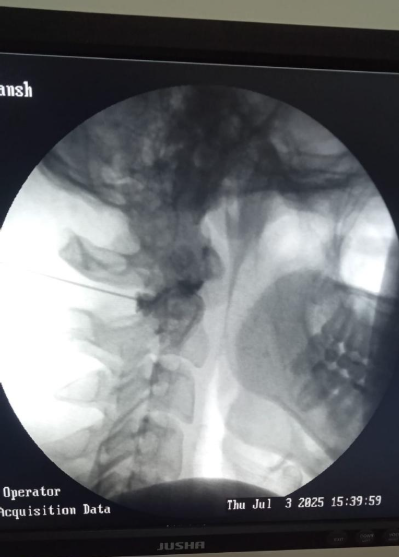

Fluoroscopy guided Intrartcular C1-C2 cervical  facet joint anti inflammatory injection at Alleviate Pain Clinic, Bengaluru. Image Courtesy- Alleviate Pain Clinic

1. Cervical Facet Joint Injection